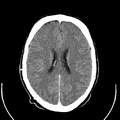

معرض الصور

يوضح ماسح التصوير المقطعي الحاسوبي بدون غلافه كيف يعمل؛ داخل الجهاز الذي يكشف عن داخلك |